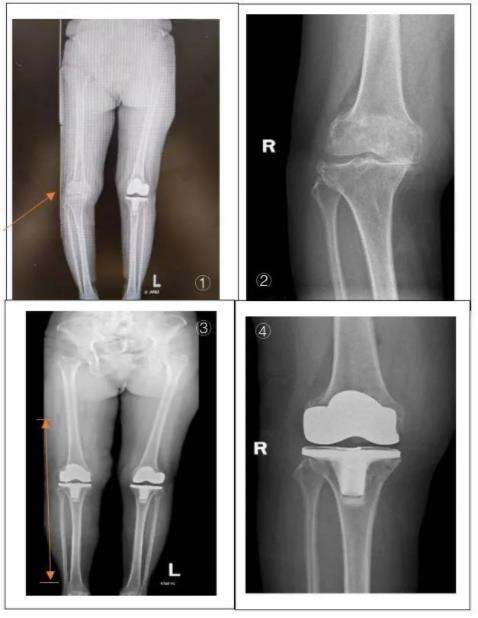

▲图①、图②患者术前影像资料显示患者右膝退变严重;图③、图④术后资料显示置换后假体位置良好,双下肢力线良好

术后第一天,医生拔除颜奶奶伤口引流管后为她进行了X线复查,显示置换后假体位置良好,双下肢力线良好。经过一系列的康复锻炼,颜奶奶术后第二天可下床行走,疼痛明显减轻,于近期办理出院。